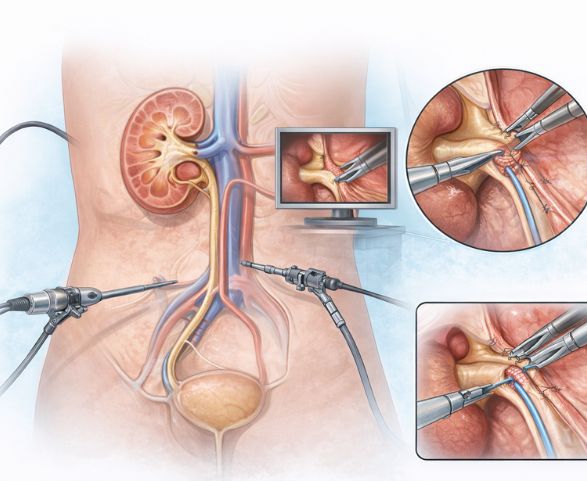

Laparoscopic Pyeloplasty is a minimally invasive surgical procedure performed to correct UPJ obstruction by removing the narrowed segment between the kidney and ureter and reconstructing it to restore normal urine flow. This advanced technique uses small keyhole incisions and specialized instruments, resulting in less pain and faster recovery compared to traditional open surgery.

Laparoscopic Pyeloplasty is advised when UPJ obstruction causes impaired urine drainage from the kidney, leading to symptoms or reduced kidney function. This minimally invasive procedure removes the narrowed segment and reconstructs the ureter to restore normal urine flow, helping preserve long-term kidney health.